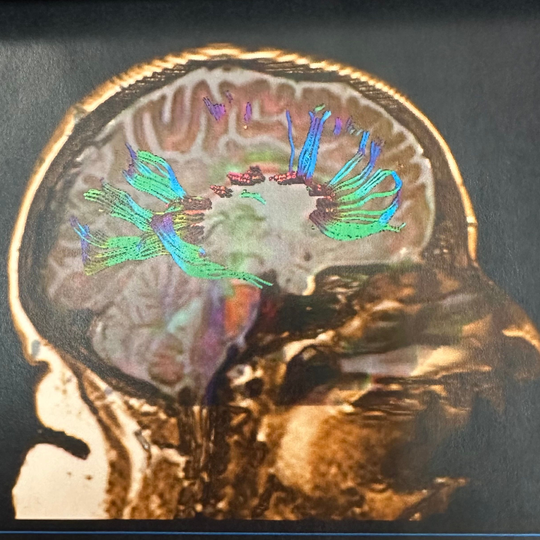

A concussion or blast injury causes a diffuse injury throughout the brain: multiple small lesions that are not detectable at a gross anatomical level. The neuropathology of the injury must be evaluated in a different way. The genius of brain MRI with DTI application is that physiological changes in the brain which represent injury are demonstrated in conjunction with tractography (the drawing of fiber tracts in the brain). Interruptions in the fiber tracts are consistent with injury at that location. Damaged fiber tracts interfere with network functions of the brain.

ABNORMAL MRI-DTI

“Blast Injury Demonstrated with MRI -DTI"

We cannot continue to misdiagnose veterans who have suffered concussion and blast injury because they are not having the most specific, diagnostic testing done. You cannot heal if you have never been properly diagnosed.